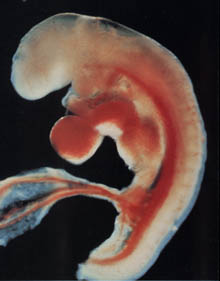

S'il y a une 4ème semaine d'obstétrique, alors il est trop tôt pour parler du fœtus. Le zygote passe progressivement au stade de l'embryon. L'enfant à naître est maintenant un bloc de cellules presque invisible, que les scientifiques appellent morula. Au microscope, il ressemblera à une baie recouverte de «boutons». Si la consolidation de la morula dans la cavité utérine ne s'est pas encore produite, elle aura certainement lieu. Et puis la vraie magie cellulaire commence.

La taille du futur fœtus au cours de la 4e semaine d'obstétrique est comparable à la «graine de pavot». Son poids est d'environ 0,5 g et sa hauteur de 0,36 à 1 mm. Cependant, ce sont des données littéralement momentanées. L'embryon augmente rapidement en raison d'une division cellulaire constante.

La structure de l'embryon

Les médecins utilisent souvent le concept du disque germinal, qui forme la feuille germinale. Ce sont des couches spéciales de cellules:

- la couche interne (endoderme) donnera naissance au tube digestif, au foie et aux poumons, ainsi qu'au pancréas;

- la couche intermédiaire (mésoderme) est constituée des futurs reins, muscles, cœur et vaisseaux sanguins, ainsi que du squelette du bébé;

- la couche externe (ectoderme) est responsable de la formation du système nerveux, de la tête (y compris les yeux, les dents et les cheveux), ainsi que de la peau.